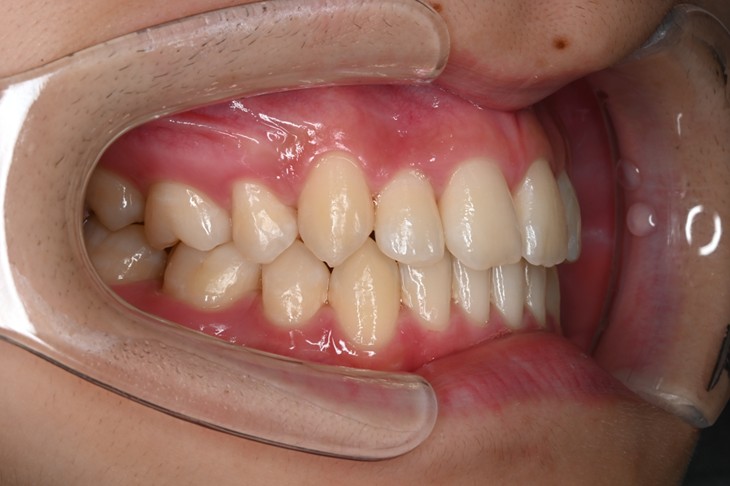

症例3:出っ歯が気になる

| 患者様データ | 20代 女性 |

| 来院主訴 | 出っ歯が気になる。 |

| 治療内容 | 出っ歯を治すために上の小臼歯を2本抜歯し、インビザラインにてマウスピース矯正を開始しました。かみ合わせを整えるためにゴムかけを行いました。 |

| 概算治療費 | 約85万円 |

| 治療期間 | 1年4ヶ月 |

| 通院回数 | 8回 |